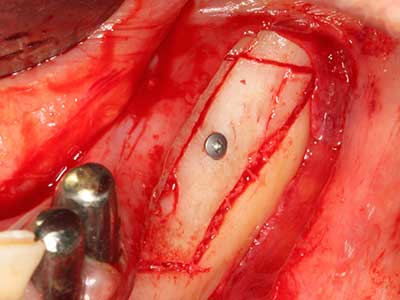

En la extracción de bloques óseos la piezocirugía también presenta ventajas adicionales: Además de la alta precisión en la osteotomía que ya se ha descrito antes, se ha comprobado que el uso de los delgados insertos de sierra resulta especialmente cuidadosas con el hueso. Frente a esto, sobre todo cuando se usan las fresas de Lindemann, cabe esperar pérdidas en la extracción significativamente más altas debido al mayor grosor de la parte frontal del cabezal (Lakshmiganthan, Gokulanathan et al. 2012). La separación basal que se necesita en particular en los injertos de bloque extraídos de forma retromolar se ve facilitada mediante sierras perpendiculares especialmente previstas a tal fin, lo que permite considerar que la cirugía piezoeléctrica es un procedimiento preciso y seguro para la obtención de bloques de hueso en el área retromolar (Happe 2007) (fig. 1-12).

El tejido óseo no solo tiene un contenido puramente mineral, sino que también presenta una importante proporción de fibras de colágeno. Esto no solo garantiza una buena resistencia a la presión, sino también una cierta flexibilidad, que puede aprovecharse para la realización de aumentos. En la plastia de expansión clásica a efectos de una partición ósea, la cresta maxilar atrofiada se divide en su eje longitudinal y, tras alcanzar una profundidad de osteotomía suficiente, se extiende con cuidado (fig. 13-16), en un caso ideal sin desperiostizar de forma visible el maxilar (Brugnami, Caiazzo et al. 2014, Stricker, Fleiner et al. 2014). Los sistemas de tornillos y placas con distancia de expansión creciente han demostrado su eficacia para distanciar entre sí las dos tablas óseas por debajo del umbral de rotura. Por regla general, se requieren anchuras de hueso residual de al menos 3 a 4 mm (Chiapasco, Zaniboni et al. 2006) para garantizar una flexibilidad y una cobertura ósea suficientes de los implantes que van a incorporarse. En caso necesario, una osteotomía de descarga vertical unilateral o bilateral puede mejorar la flexibilidad. Como alternativa a la técnica clásica se ha descrito una combinación con otras técnicas de aumento, sobre todo en la parte bucal.

Con el uso de sierras piezoeléctricas la división se efectúa de forma especialmente cuidadosa y sin pérdidas importantes de las dimensiones, por lo que no se han encontrado diferencias significativas entre los implantes realizados en el maxilar dividido y en la cresta alveolar no deficitaria (Chiapasco, Zaniboni et al. 2006, Danza, Guidi et al. 2009). No obstante, precisamente en la partición profunda y limitada de forma local, es preciso asegurarse de que exista una adecuada irrigación por agua para evitar que se produzcan sobrecargas térmicas en las áreas de osteotomía apical.